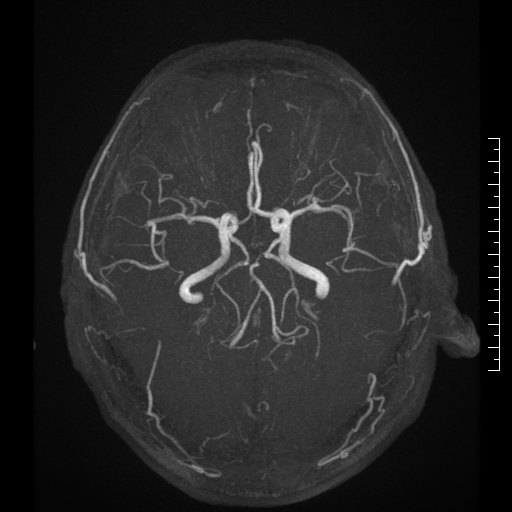

颅脑血管MRA功能检查:脑血管筛查的重要手段,对脑血管狭窄,脑动脉瘤和脑血管畸形都可以做一个初步诊断和评估,优点是不需要对比剂,无创和无辐射的,脑血管筛查的重要手段,对脑血管狭窄,脑动脉瘤和脑血管畸形都可以做初步诊断和评估,优点是不需要对比剂,无创和无辐射的。